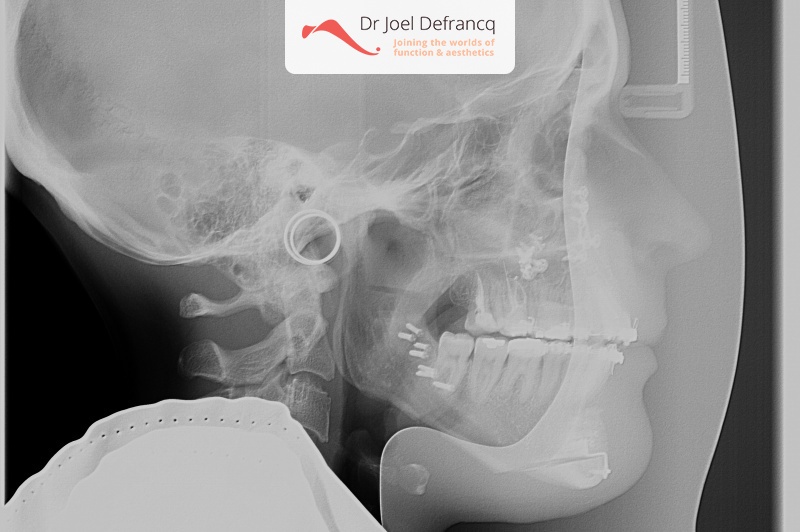

Schila: Open Beet

Diagnose van het gezicht

- Asymmetrisch gezicht

- Open beet

Dentale diagnose

Kaakchirurgie

- Vertikale verkorting bovenkaak (Le Fort I)

- Kinchirurgie

Esthetische chirurgie

- Neuscorrectie (rhinoplasty)